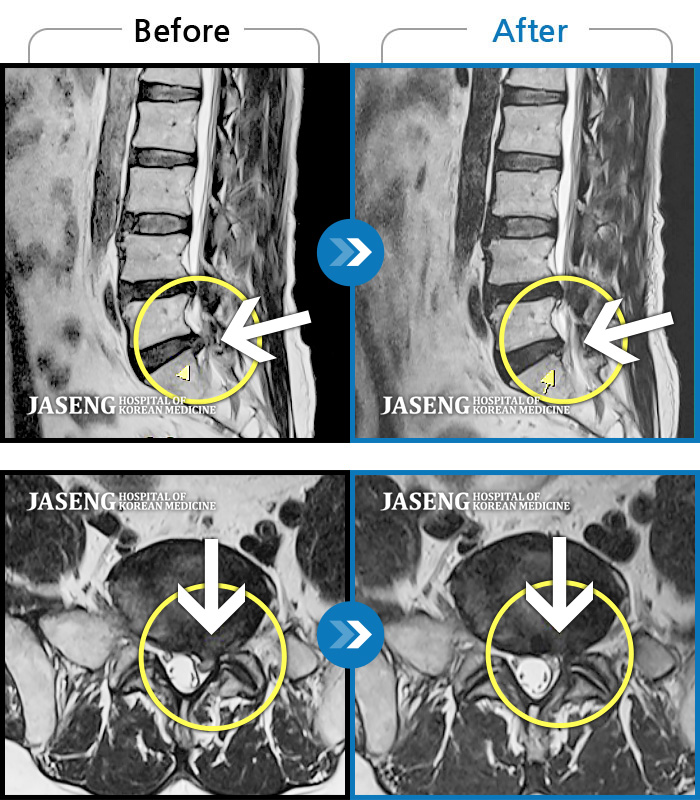

허리디스크

도움받은 사례

광주 · 장영우 원장

좌측 허리 통증으로 허리를 반듯이 펴고 서있기 힘들어 내원하셨습니다.

촬영시기

2024.08.12 ~ 2025.02.26

2025.03.07